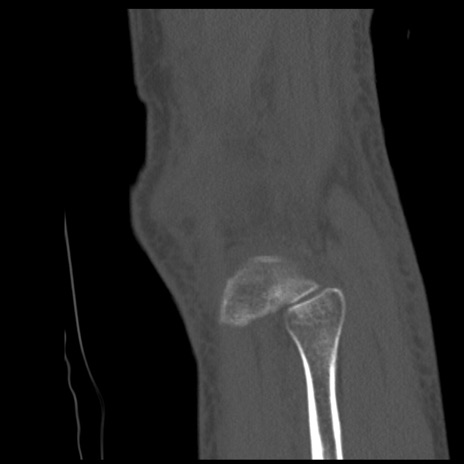

症例28 右膝関節CT(矢状断像)

右膝関節CT